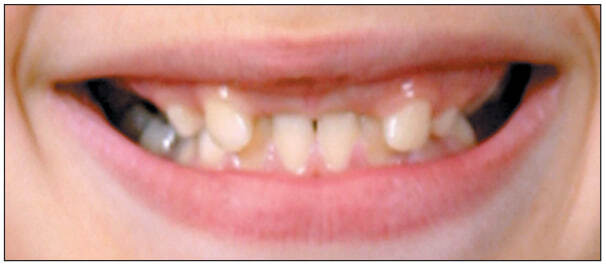

Клинический случай Пациент Ф.А., 10 лет, обратился в 2009 году с жалобами на отсутствие передних зубов верхней челюсти и боковых зубов нижней челюсти. При осмотре выявлены дефекты зубных рядов во фронтальном отделе верхней челюсти (рис. 1) и боковых отделах нижней челюсти.

Рис. 1. Дефект верхнего зубного ряда верхней челюсти Ф. А., 10 лет